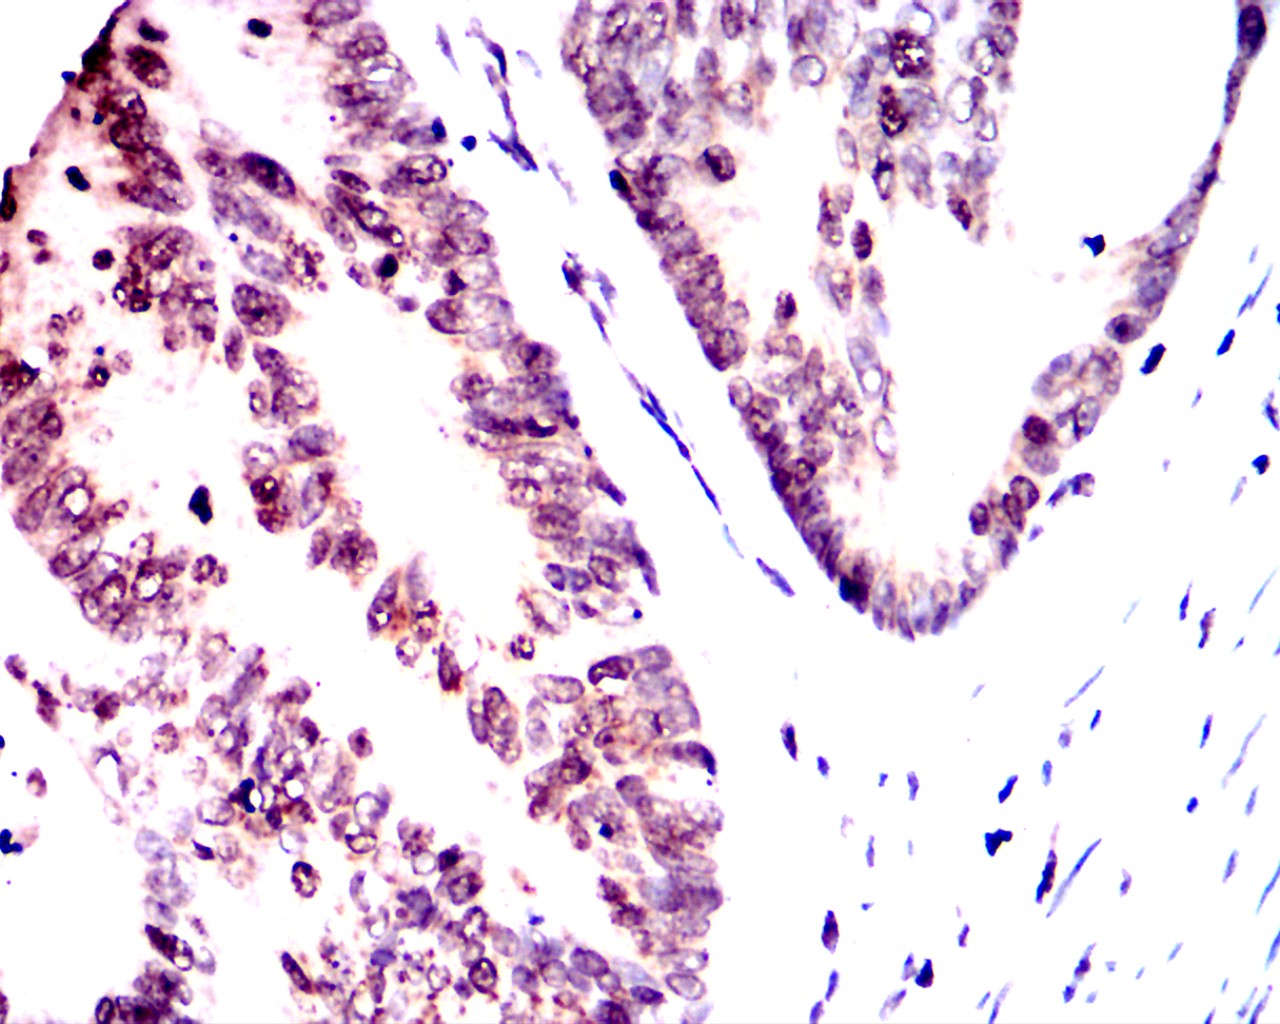

Immunohistochemical analysis of paraffin-embedded breast cancer tissues using OTX2 antibody with DAB staining.Pre-treat the sections with heat-mediated antigen retrieval using sodium citrate buffer (pH 6.0) (OM750020) for 2 minutes. Wash the sections with ddH₂O and PBS (OM750003). Block the tissue with 10% non-immune goat serum(OM760028) at room temperature for 30 minutes. Incubate the tissue with the primary antibody diluted at a ratio of 1:1500 at 4°C overnight. At room temperature, dilute the secondary antibody, Goat Anti-Mouse IgG (H&L) - HRP(OM644366), at a ratio of 1:200 and incubate for one hour. Use DAB(OM760029)as the chromogenic agent. Counterstain the tissue with hematoxylin, and mount the tissue sections with neutral gum.IHC

Immunohistochemical analysis of paraffin-embedded breast cancer tissues using OTX2 antibody with DAB staining.Pre-treat the sections with heat-mediated antigen retrieval using sodium citrate buffer (pH 6.0) (OM750020) for 2 minutes. Wash the sections with ddH₂O and PBS (OM750003). Block the tissue with 10% non-immune goat serum(OM760028) at room temperature for 30 minutes. Incubate the tissue with the primary antibody diluted at a ratio of 1:1500 at 4°C overnight. At room temperature, dilute the secondary antibody, Goat Anti-Mouse IgG (H&L) - HRP(OM644366), at a ratio of 1:200 and incubate for one hour. Use DAB(OM760029)as the chromogenic agent. Counterstain the tissue with hematoxylin, and mount the tissue sections with neutral gum.